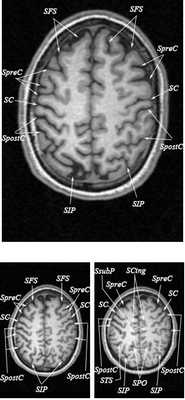

МРТ головного мозга. Т2-взвешенная аксиальная МРТ. Цветовая обработка изображения.

Знание анатомии мозга очень важно для правильной локализации патологических процессов. Ещё более важно оно для изучения самого мозга с помощью современных «функциональных» методов, таких как функциональная магнитно-резонансная томография (fMRI), и позитронно-эмиссионная томография. С анатомией мозга мы знакомимся ещё со студенческой скамьи и существует множество анатомических атласов, в том числе и поперечных сечений. Казалось бы, зачем ещё один? На самом деле, сравнение МРТ срезов с анатомическими приводит к множеству ошибок. Это связано как со специфическими особенностями получения МРТ изображений, так и с тем, что строение мозга очень индивидуально.

Представленная страница сайта основана на специальном изучении МРТ головного мозга здоровых лиц. Для этого изображения получали с минимальной величиной воксела (1 мм в каждом измерении), что исключало наслоения борозд. Каждая из структур прослеживалась в трёх реконструированных плоскостях путём её выделения с помощью компьютерной программы. Мы рассматривали различные анатомические варианты, что обсуждается в работе. В результате, учитывая вариабельность строения мозга, подобран условно «стандартный» мозг. Поскольку на сайте нереально представить 128 срезов в каждой из основных плоскостей, мы ограничились только каждым пятым срезом. Основные срезы в поперечной плоскости даны без наклона назад (угол 0º). Под ними для представления о изменении соотношения анатомических структур демонстрируются срезы, выполненные на тех же уровнях, но с наклонами назад -15º и -30º.

Поперечные (аксиальные) МРТ срезы головного мозга